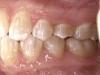

Figure 14  The patient#8217;s smile was affected by her collapsed premolars and molars, resulting excessive buccal corridor.s

Figure 14

Figure 17  Buccal corridors were improved through premolar uprighting. With bimaxillary advancement, a wider portion of the maxilla and mandible was moved forward into the lip drape, reducing the size of the buccal corridor.

Figure 17